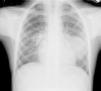

Varón de 8 años, procedente del medio rural marroquí, con accesos de tos crónica, productiva y hemoptisis ocasional de 6 meses de evolución. Afebril y sin otra sintomatología, presenta buen estado general, ausencia de dificultad respiratoria y buena ventilación pulmonar generalizada. Se desconocen tratamientos y estudios previos. En la radiografía de tórax (PA y lateral) (figs. 1 y 2) se aprecia condensación homogénea redondeada de contornos definidos, borrando silueta cardiaca en língula. Sin broncograma aéreo asociado. Perfil general y reactantes de fase aguda, normales. Leucocitos 4.400/ml3. Serologías de neumonía y Mantoux, negativos. Plantea diagnóstico diferencial con malformación pulmonar congénita (quiste broncógeno) y, considerando la procedencia del paciente, quiste hidatídico1. Se solicita TC torácica y serología a Echinococcus granulosus. Se evidencian en la ventana pulmonar (fig. 3) dos masas ovoideas bien definidas, con hipoatenuación central y sin participación pleural. La primera, de 32mm de diámetro (segmento 6 de LID), contacta con cisura mayor. La segunda era de 44mm, en la língula (segmento 4). Resto del parénquima pulmonar, sin otras masas ni nódulos. Mediastino sin adenopatías. La IgE específica a E. granulosus (8,38 KU/l), confirmada mediante hemaglutinación a hidatidosis2 (1/10.240), sugiere que las masas sean quistes hidatídicos. Ecografía abdominal sin afectación hepática. Se traslada al centro de referencia de cirugía infantil para tratamiento quirúrgico y confirmación anatomopatológica.